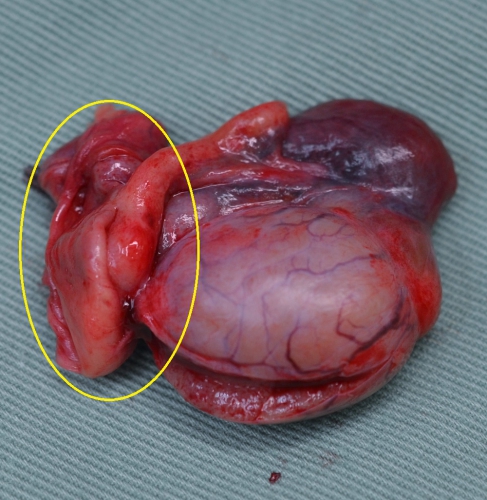

下の写真が精巣・精巣上体炎を起こした犬の精巣上体を黄色丸印で示しています。右が正常、左が精巣上体炎の見られた睾丸です。2週間程度の抗生物質による治療後にも痛みと腫れが残ったため、症状の緩和のために去勢手術を実施したものです。当初の著しい腫れは見られませんが、全体的にかなり赤みを帯びており、精巣上体は明らかに硬い印象がみられました。